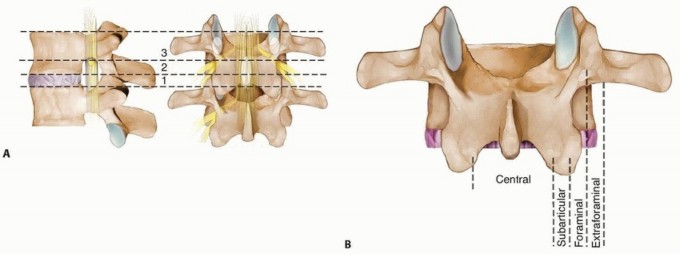

Lumbar Discectomy DEFINITION Clinically significant lumbar disc herniations are characterized by a focal dist…